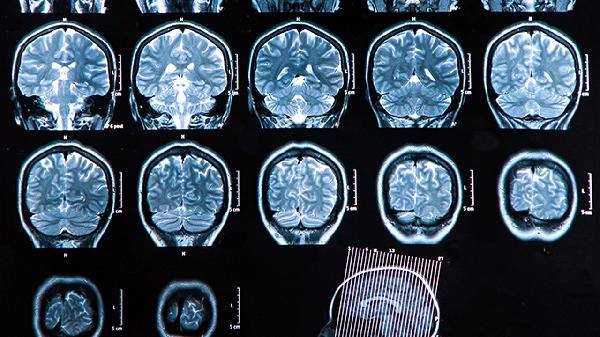

宝宝大脑发育的黄金时期通常指胎儿期至3岁,尤其是出生后前12个月。这一阶段神经元快速增殖、突触形成,受遗传、营养、环境刺激等因素共同影响。

新生儿脑重约为成人的25%,6个月时增长至50%。此阶段突触密度达到高峰,需通过母乳喂养提供胆固醇、铁等必需物质。家长应多进行面对面交流、抚触,促进视觉听觉通路发育。睡眠周期规律对突触修剪至关重要。